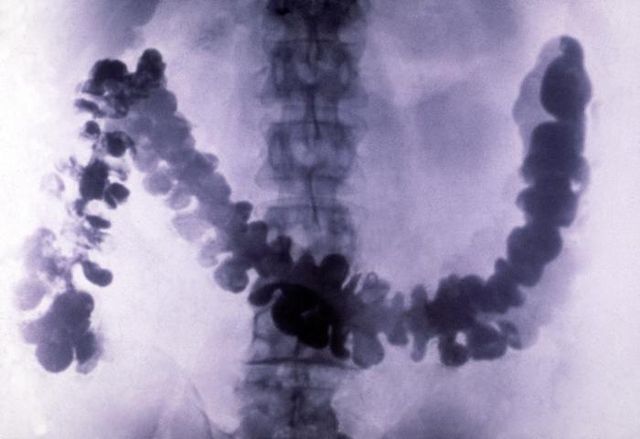

Amoebiasis as seen in radiograph of barium-filled colon |